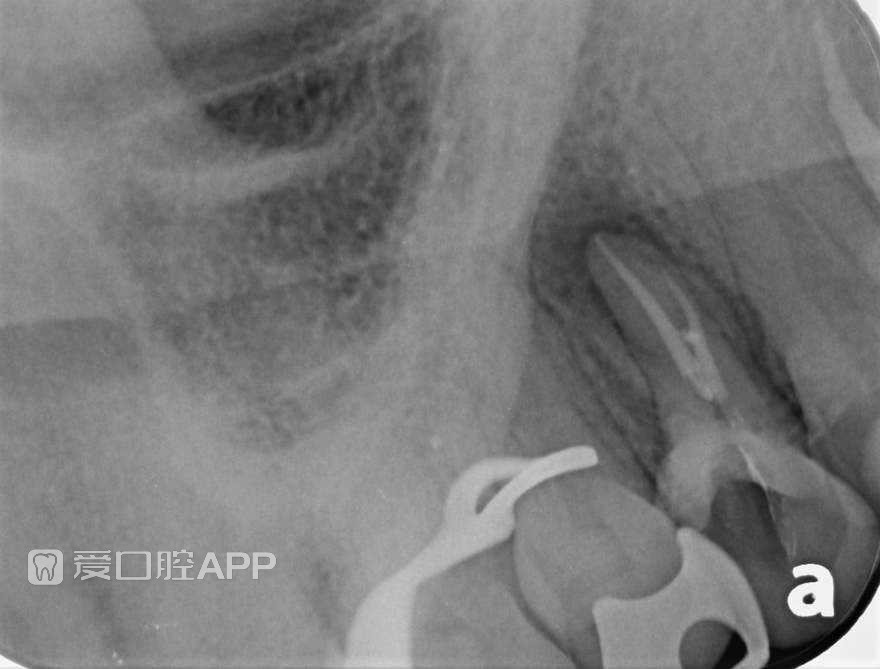

上颌第一前磨牙根管治疗1例

By Jorge Zapata